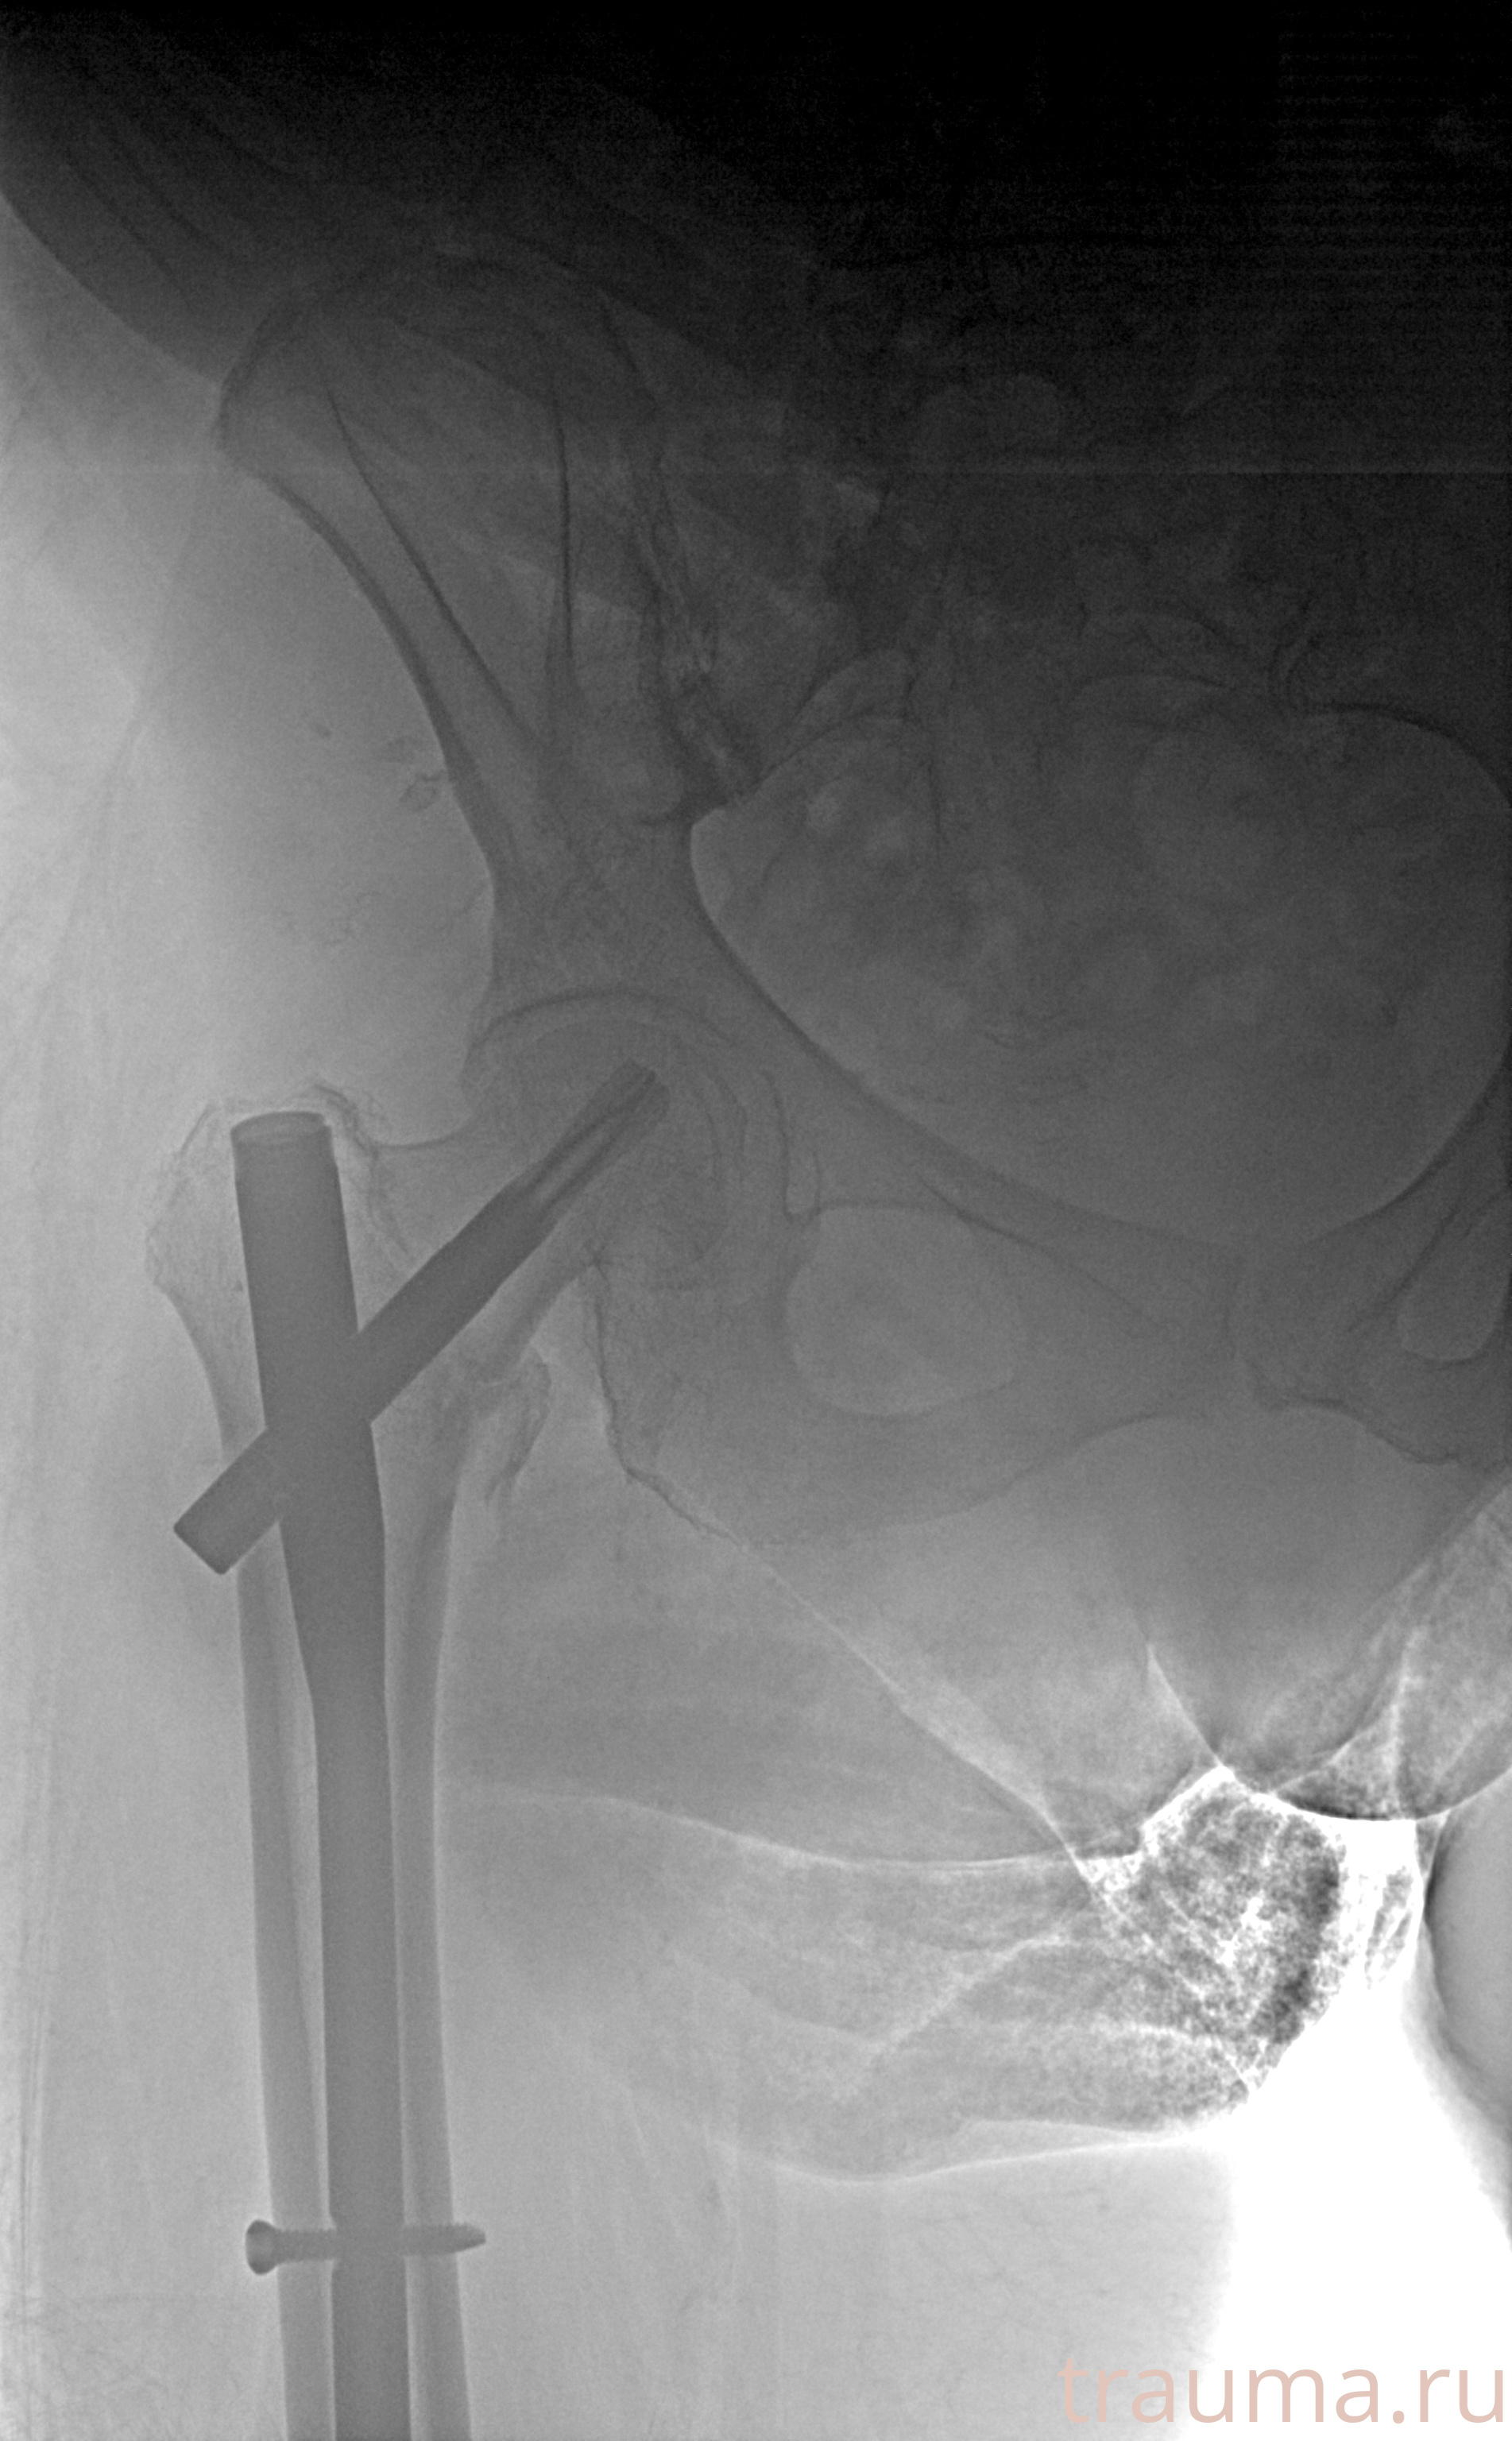

Рентгенограммы

Рентген на дому: по вашему адресу приезжает врач-рентгенолог, травматолог-ортопед с мобильным рентгеновским аппаратом, проводит диагностику травмы или заболевания, делает необходимые рентгенограммы, дает рекомендации по дальнейшему лечению. Получить качественные снимки в домашних условиях возможно благодаря уникальной методике, разработанной МосРентген Центром для института  Склифосовского